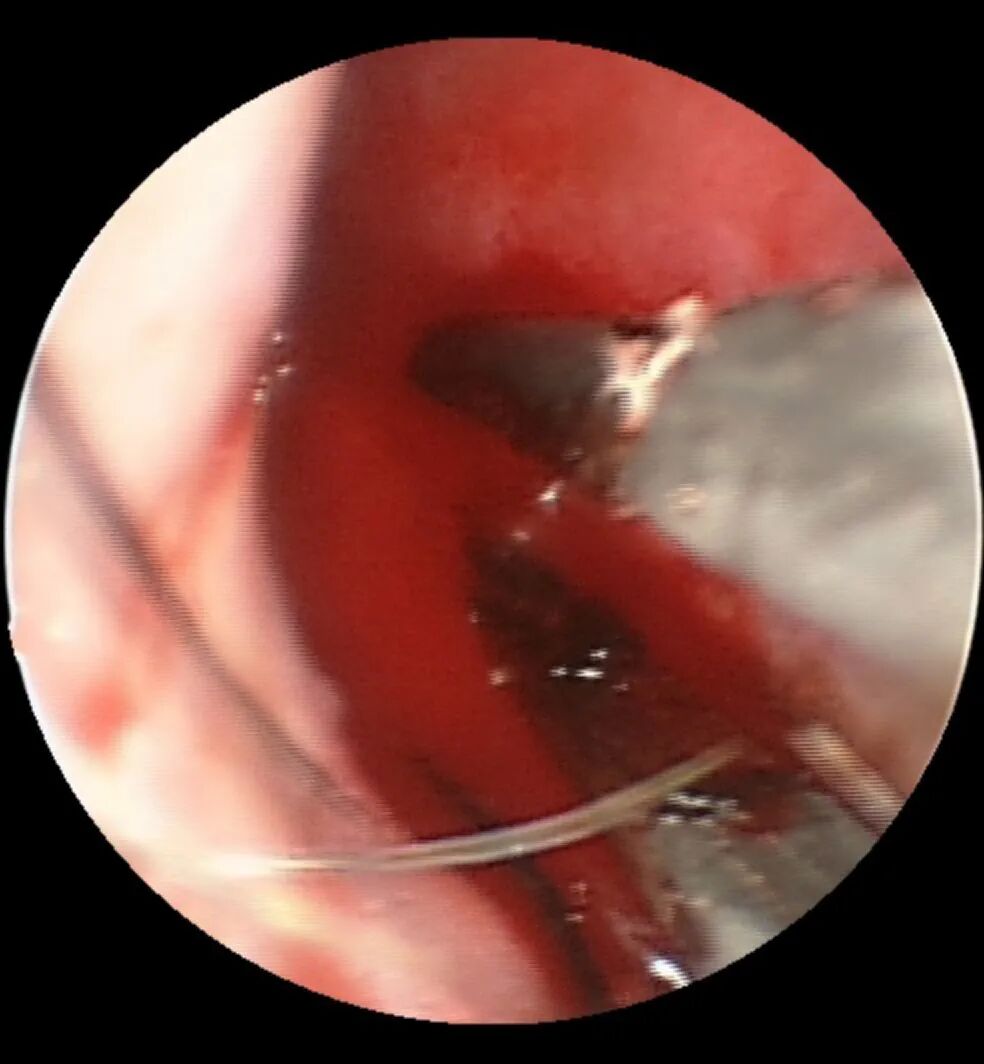

2.下一步需要使用双极电凝进行局部电凝止血,也就是在出血部位的粘膜进行电刺激使粘膜形成血栓封闭出血动脉,达到控制出血的目的,如下图所示:

图:予电凝烧灼